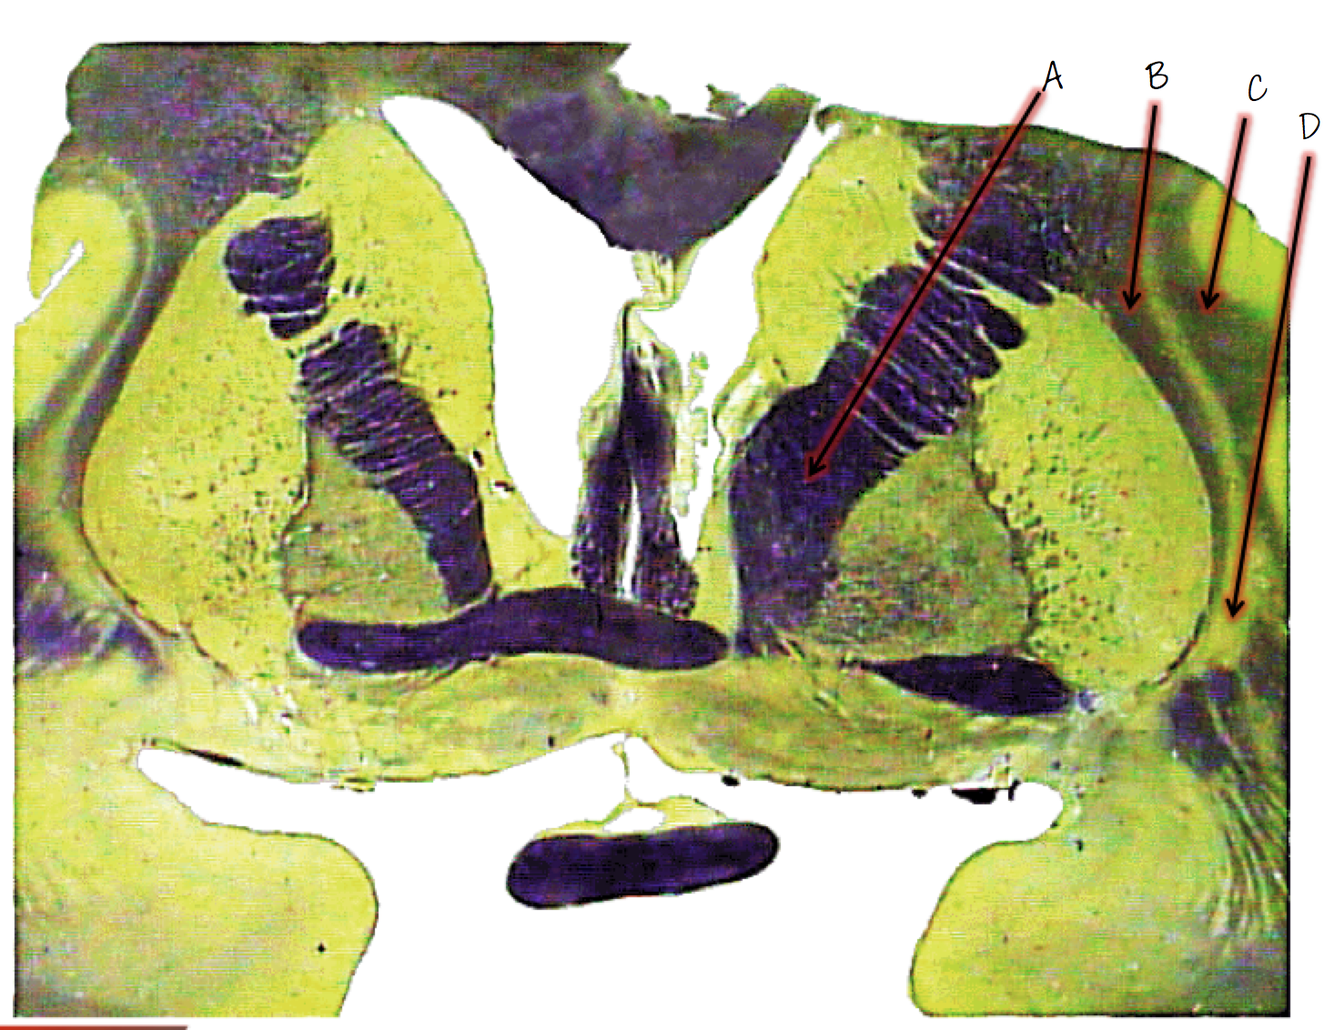

A; lateral ventricle

B; choroid plexus

C; corpus callosum

D; fornix

E; third ventricle